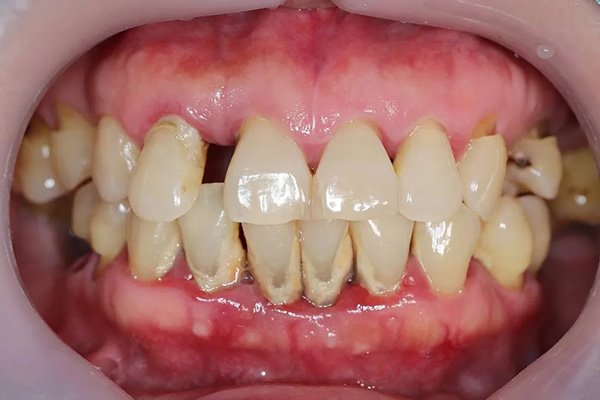

牙周病(圖片來源:Periodontitis (Gum Disease): Symptoms, Causes, and Treatments)

究竟植體周圍炎和一般牙周病差在哪裡呢?以下是它們的五個主要差別:

- 發炎位置不同

牙周病是發生在自然牙的牙根周圍。而植體周圍炎則是發生在「人工牙根(植體)」的周邊組織,這是因為植體是金屬材質,沒有自然牙的防護韌帶,細菌更容易直接侵入齒槽骨。 - 齒槽骨發炎症狀更明顯